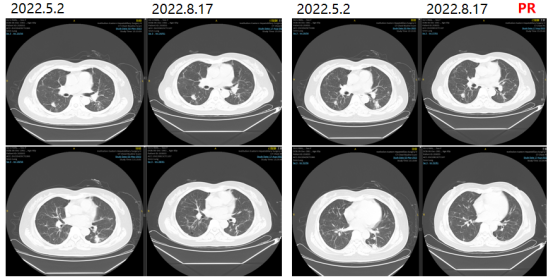

更换治疗方案为西妥昔单抗+SIRI治疗。2022-06-24、2022-07-20分别予西妥昔单抗+SIRI方案q3w。

图4影像学复查结果

2022-12-14复查胸部CT提示两肺多发转移瘤,较前进展。PFS3:7月。